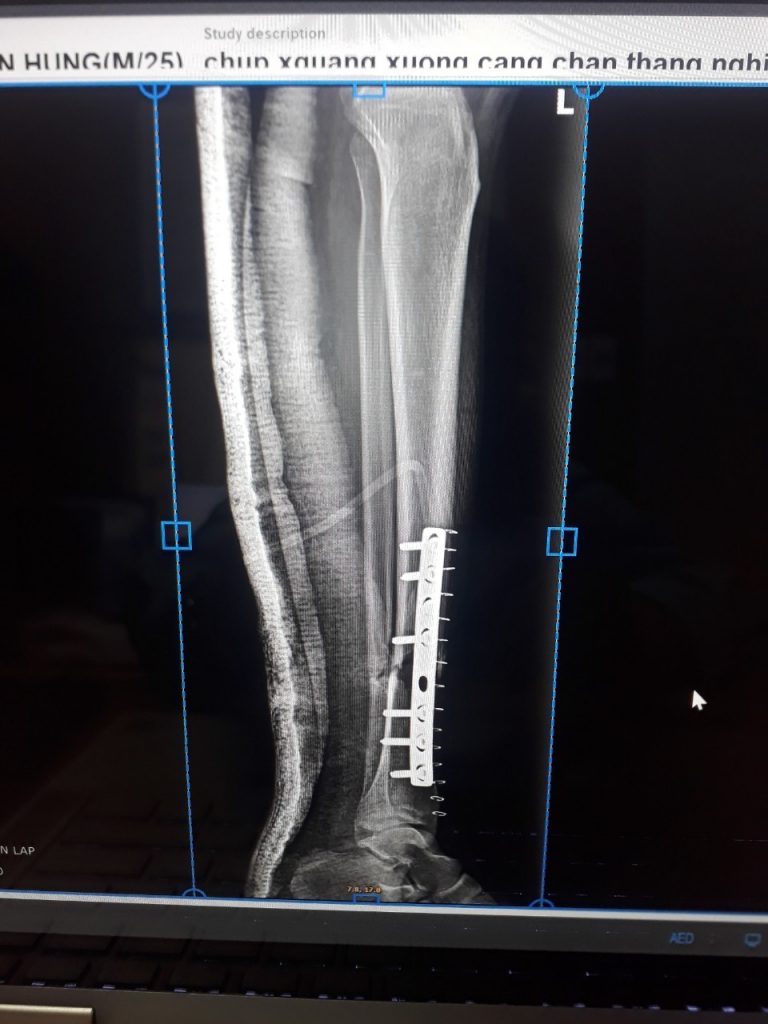

Ngày 25/10/2022, anh B.V.H, sinh năm 1997, ở xã Xuân Viên, huyện Yên Lập, tỉnh Phú Thọ được gia đình đưa đến cấp cứu tại Trung tâm Y tế huyện Yên Lập. Theo lời kể của gia đình, người bệnh đi xe máy bị ngã, sau ngã tỉnh, đau nhức, mất vận động chân trái, […]